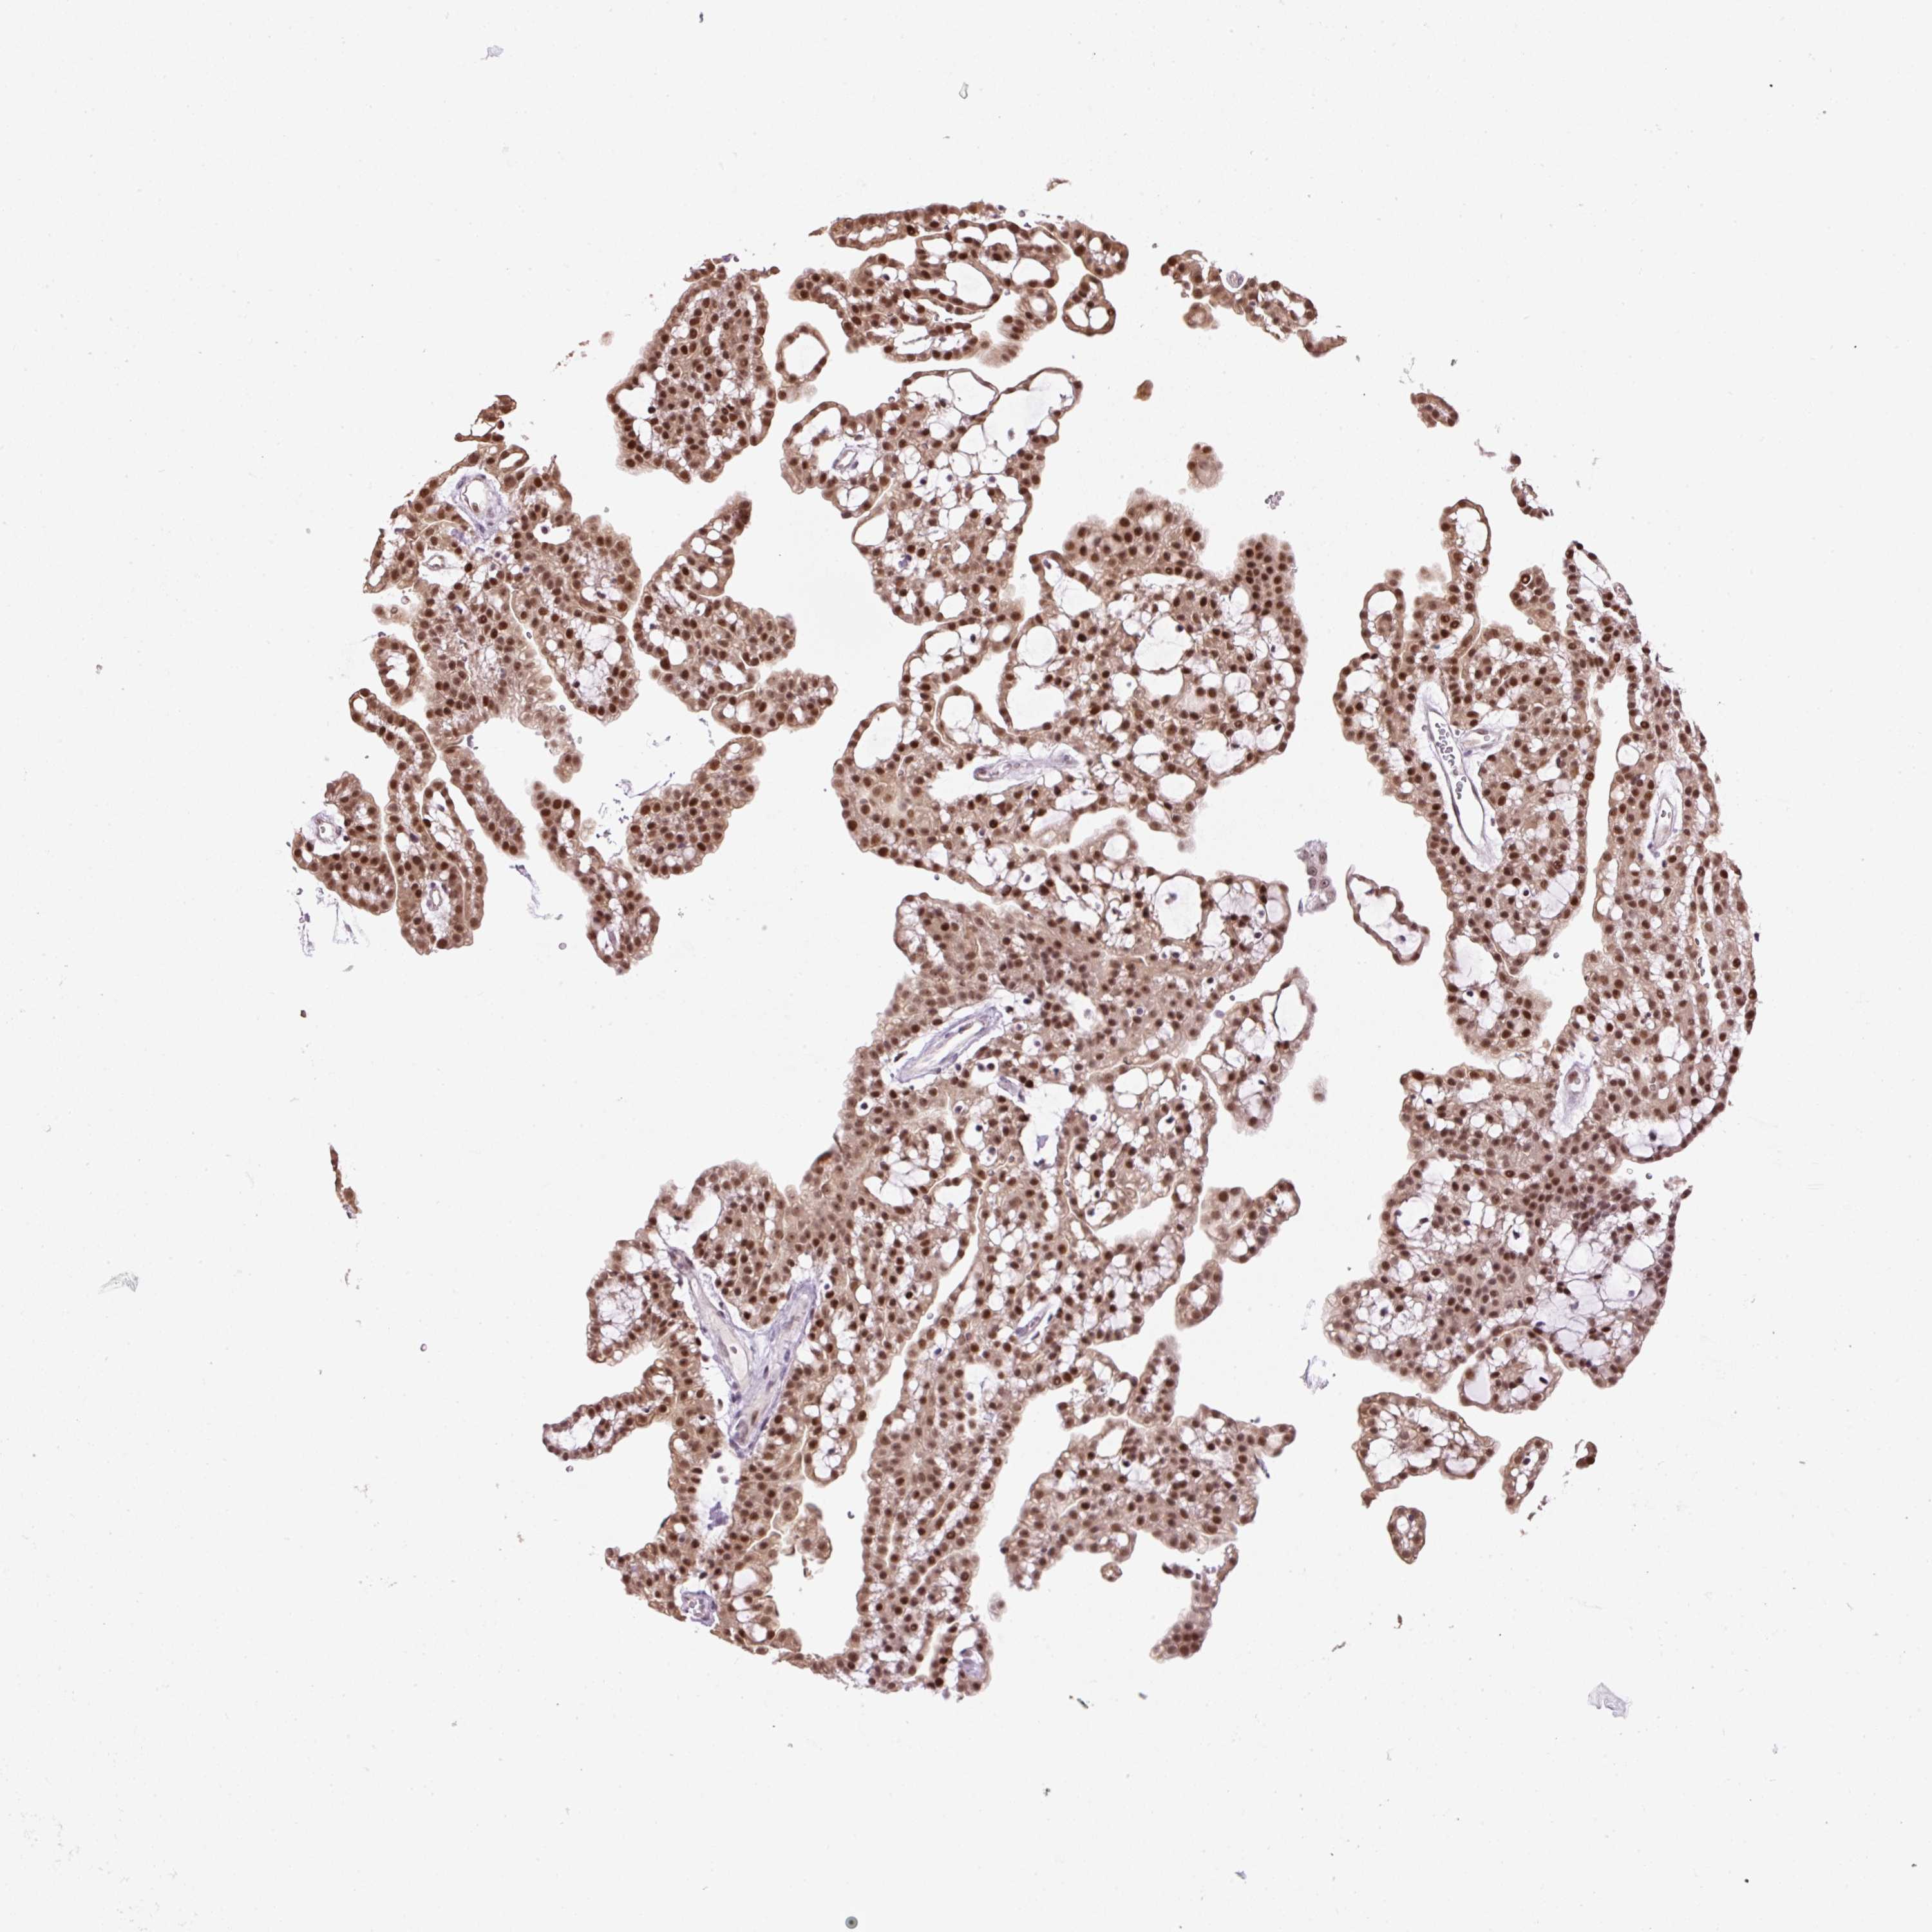

KIDNEY RENAL CLEAR CELL CARCINOMA (VALIDATION) - Interactive survival scatter ploti

The Survival Scatter plot shows the clinical status (i.e. dead or alive) for all individuals in the patient cohort, based on the same data that underlies the corresponding Kaplan-Meier plots. Patients that are alive at last time for follow-up are shown in blue and patients who have died during the study are shown in red.

The x-axis shows the expression levels (FPKM) of the investigated gene in the tumor tissue at the time of diagnosis. The y-axis shows the follow-up time after diagnosis (years). Both axes are complimented with kernel density curves demonstrating the data density over the axes. The top density plot shows the expression levels (FPKM) distribution among dead (red) and alive patients (blue). The right density plot shows the data density of the survived years of dead patients with high and low expression levels respectively, stratified using the cutoff indicated by the vertical dashed line through the Survival Scatter plot. This cutoff is automatically defined based on the FPKM cutoff that minimizes the p-score. The cutoff can be changed by dragging the vertical line or by entering a cutoff value in the square labeled "Current cut-off".

Under the Survival Scatter plot the p-score landscape (black curve; left axis) is shown together with dead median separation (red curve; right axis). Dead median separation is the difference in median mRNA expression between patients who have died with high and low expression, respectively. It is calculated as follows: median FPKM expression of dead patients with high expression - median FPKM expression of dead patients with low expression. This is intended to aid the user in visually exploring custom cutoffs and the associated p-scores and dead median separation.

Individual patient data is displayed and can be filtered by clicking on one or more of the category buttons on the top of the page. Categories describing expression level and patient information include: high, low, alive, dead, female, male and tumor stages. The scale of the x-axis can be toggled between linear and log-scale by clicking on the "x log" button. Mouse-over function shows TCGA ID, patient information and mRNA expression (FPKM) for each patient.

& Survival analysisi

Kaplan-Meier plots summarize results from analysis of correlation between mRNA expression level and patient survival. Patients were divided based on level of expression into one of the two groups "low" (under cut off) or "high" (over cut off). X-axis shows time for survival (years) and y-axis shows the probability of survival, where 1.0 corresponds to 100 percent.

TAF1A is not prognostic in Kidney Renal Clear Cell Carcinoma (validation)

Best expression cut offi

Based on the FPKM value of each gene, patients were classified into two groups and association between prognosis (survival) and gene expression (FPKM) was examined. The best expression cut-off refers the FPKM value that yields maximal difference with regard to survival between the two groups at the lowest log-rank P-value. Best expression cut-off was selected based on survival analysis .

When clicking on this number, the vertical dashed line indicating cut-off, the interactive survival plot, and the Kaplan-Meier curve will be adjusted to show results based on the best expression cut-off.

: 2.28

TCGA RNA samplesi

RNA-seq data is reported as average FPKM (number Fragments Per Kilobase of exon per Million reads), generated by the The Cancer Genome Atlas (TCGA) .

Normal distribution across the dataset is visualized with box plots, shown as median and 25th and 75th percentiles. Points are displayed as outliers if they are above or below 1.5 times the interquartile range. FPKM values of the individual samples are presented next to the box plot.

Average pTPM 3.6

Number of samples 100